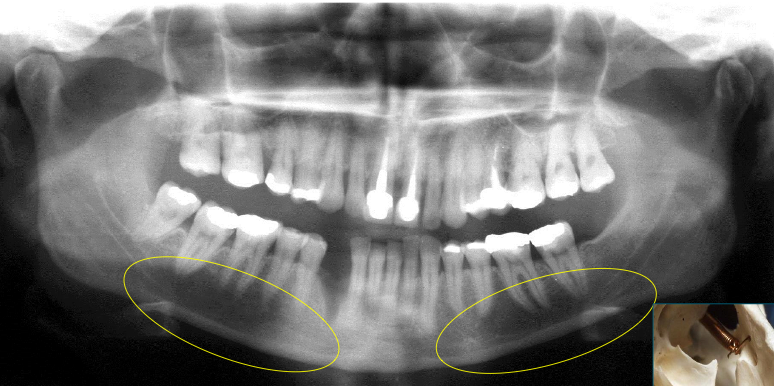

What do the submandibular fossa look like on a radiograph?

See image